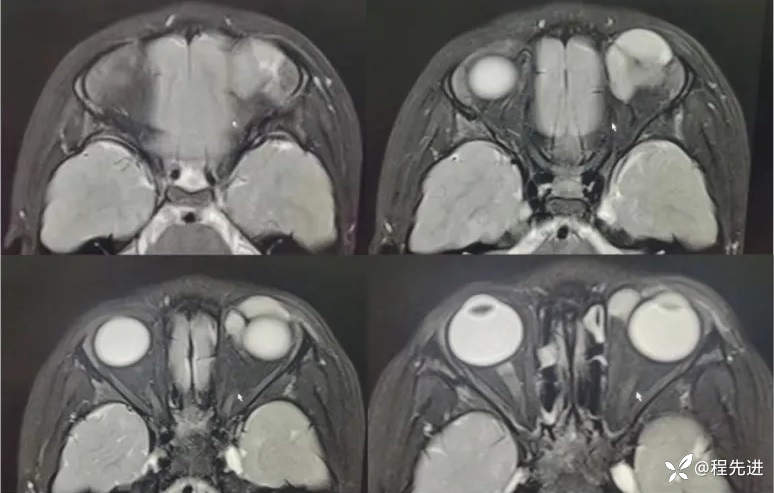

MRI平扫+增强:

T1增强: